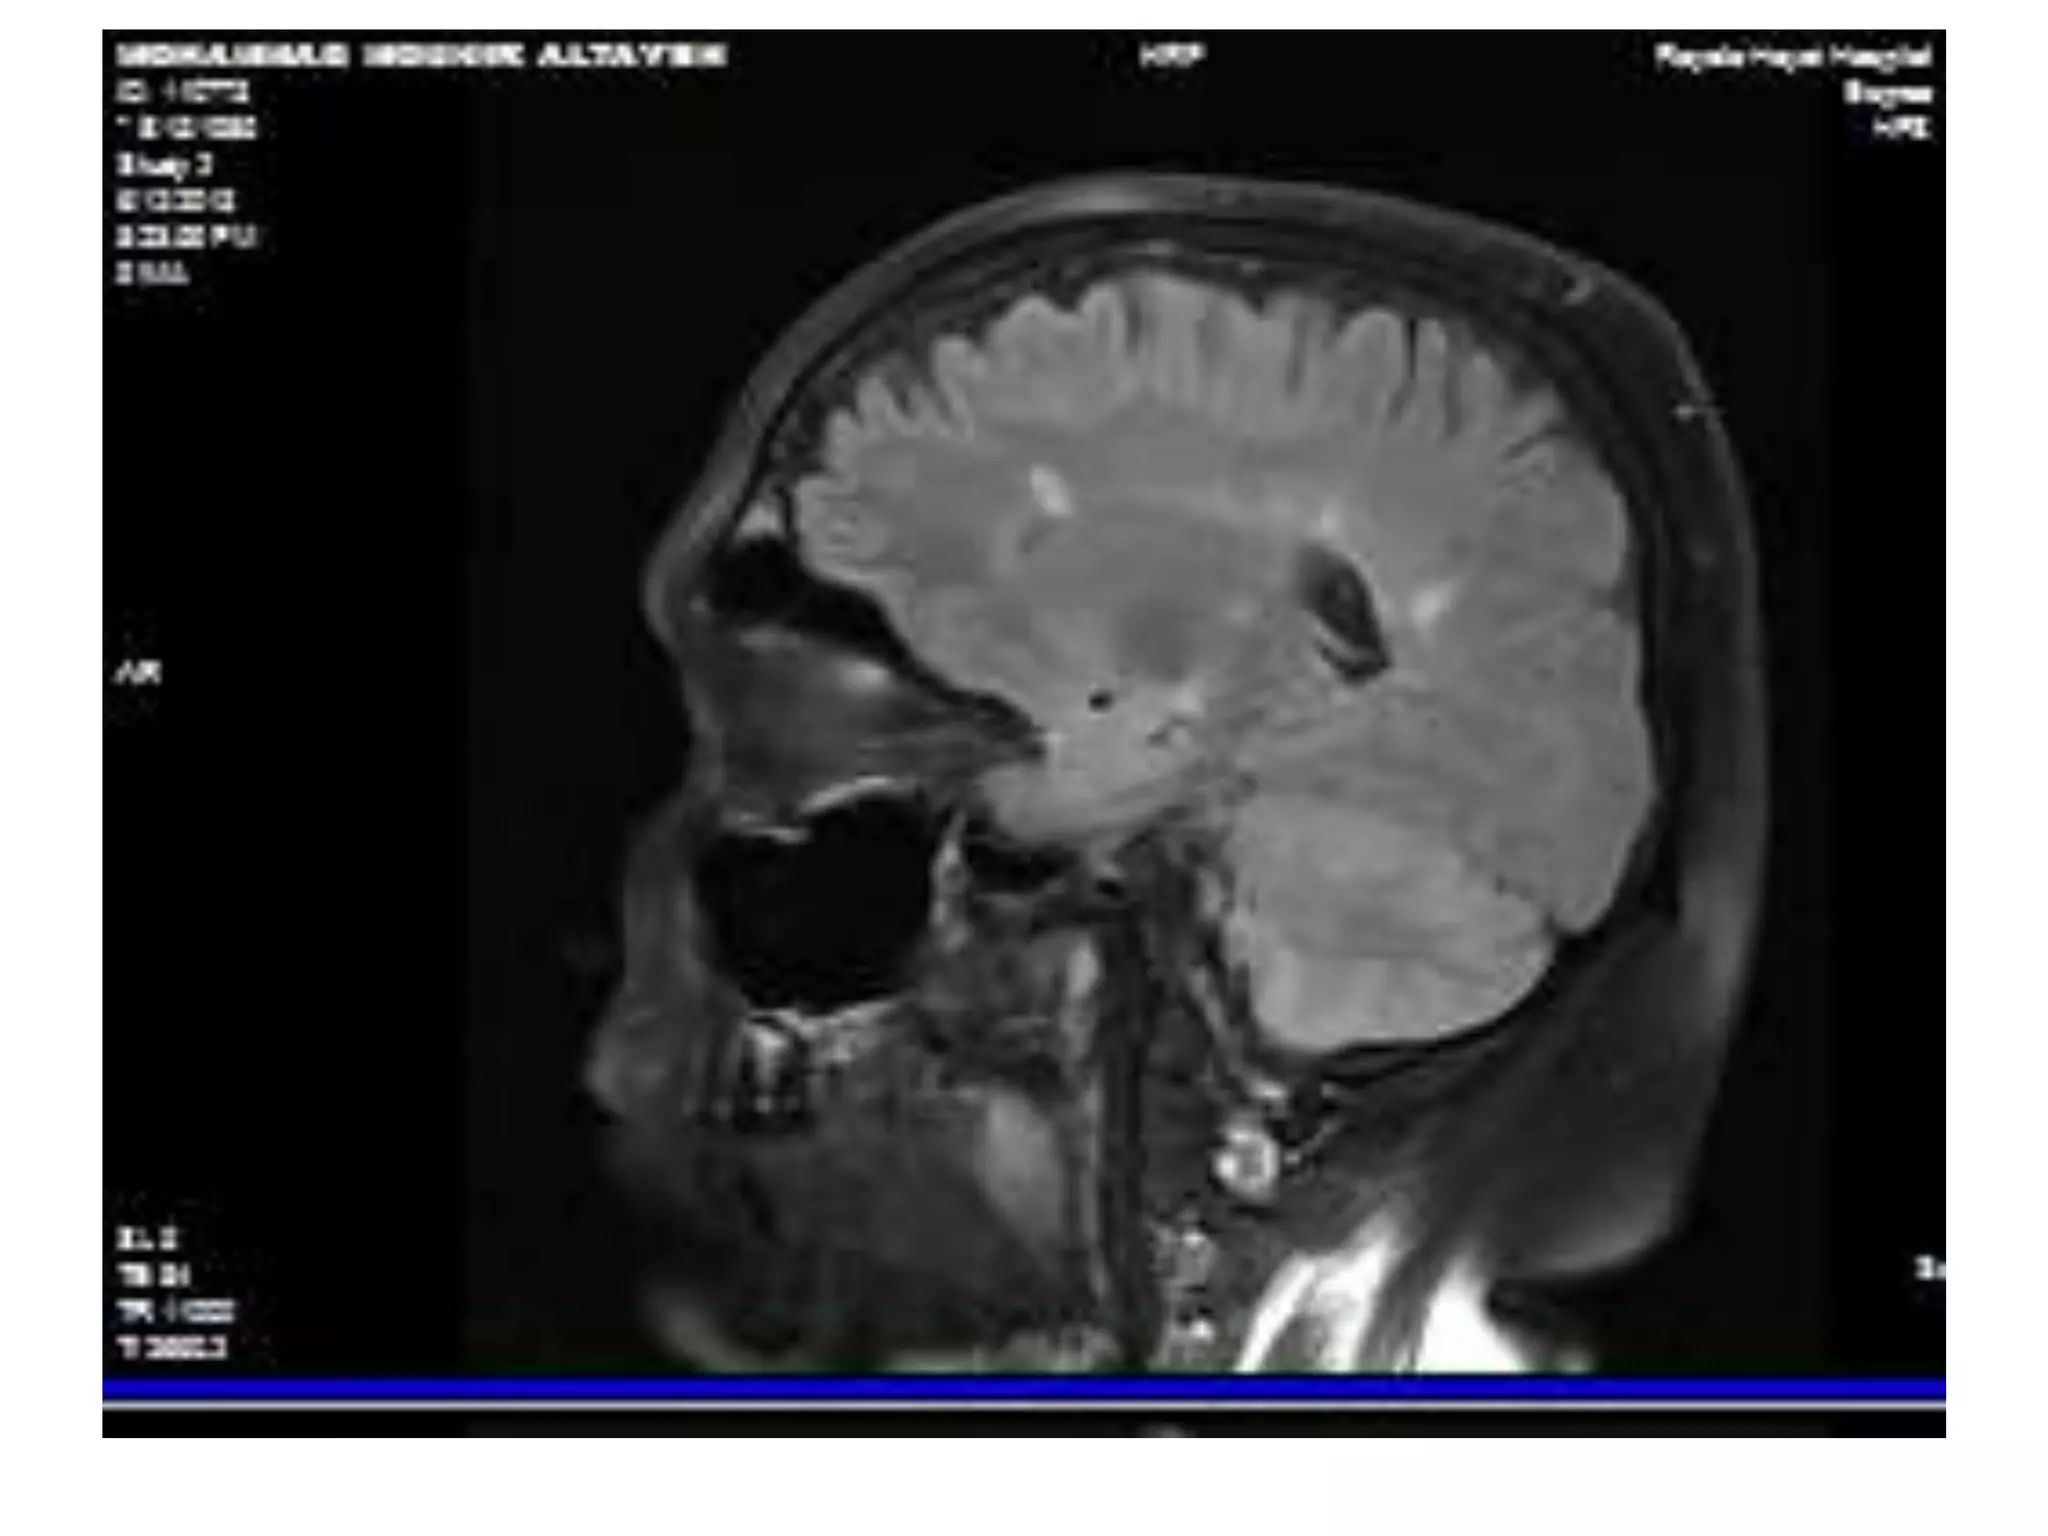

MRI Brain DIS

MRI Cervical spine: DIS